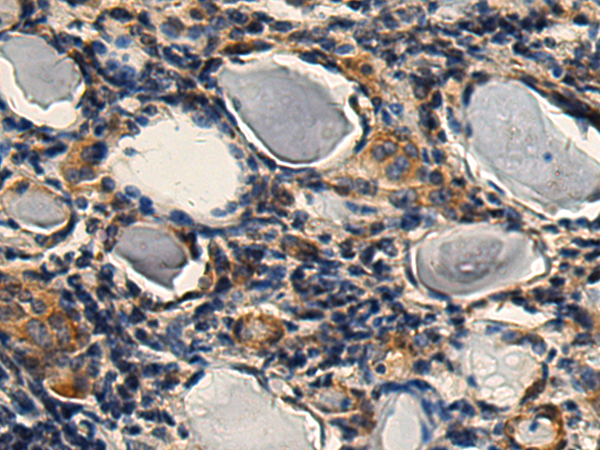

分类: 科研抗体货号: P03400别名: SORD1; HEL-S-95n应用: IHC反应种属: Human, Mouse